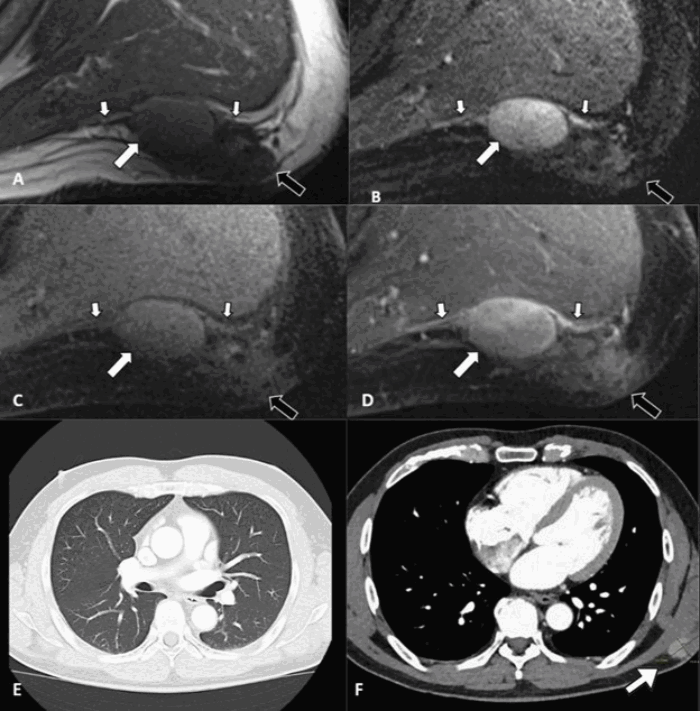

Figure 5. Preoperative MRI and Staging CT Scans. Published with Permission

(A-D) Multiplanar MRI of the mass. (A) T1-weighted, (B) T2-weighted with fat suppression, (C) T1-weighted with fat suppression, and (D) T1-weighted with fat suppression post-contrast images demonstrate a heterogeneous mass centered in the posterolateral subcutaneous fat. The lesion shows intermediate T1 signal, hyperintense T2 signal, and avid enhancement (arrows). An enhancing “tail” is seen emanating from the mass along the muscle fascia (small arrows), concerning for disease involvement, while a less-defined area of signal change more posteriorly (black arrow) likely represents postsurgical inflammation. (E, F) Axial contrast-enhanced CT images for staging. (E) CT of the chest reveals no evidence of pulmonary metastasis. (F) CT of the primary site shows the 3.3 × 1.9 cm subcutaneous mass.

Following these pathological results, the patient was re-evaluated by the surgical oncology service (Figure 4). A magnetic resonance imaging (MRI) scan revealed a residual heterogeneous mass centered in the posterolateral subcutaneous adipose tissue, and staging CT scans showed no evidence of regional or distant metastasis (Figure 5). A wide local excision (WLE) was recommended to achieve negative margins. The procedure was performed, with resection carried down to and including the underlying fascia. Final margins were negative: the deep margin was 0.2 cm (with fascia confirmed histologically), the superior margin was 1.1 cm, and all other margins exceeded 1.5 cm. Pathological examination of the resected specimen noted areas of florid giant cell and histiocytic reaction adjacent to the primary tumor. A complex, multilayered closure of the surgical defect was performed by the plastic surgery team, and the patient was discharged home on the same day (Figure 6). Based on the surgical correlation with the final, comprehensive pathological findings, a definitive diagnosis of PDS was established.